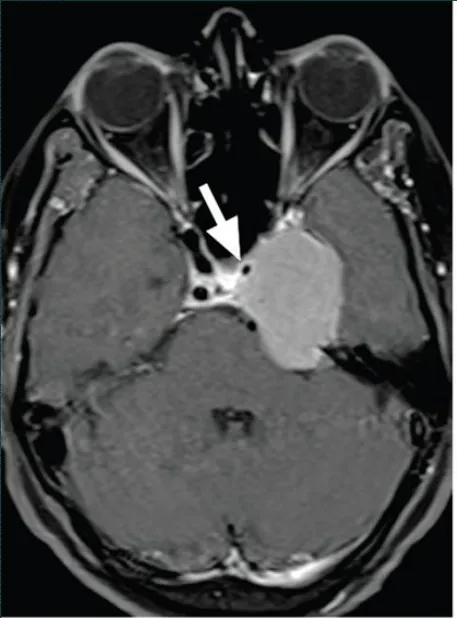

典型病例影像学表现

海绵窦脑膜瘤合并左侧颈内动脉狭窄,手术难度显著增加